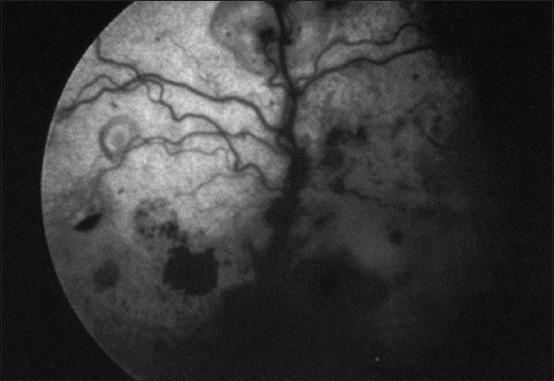

Feline infectious peritonitis (FIP) is an infectious disease characterized by non-specific laboratory changes and clinical signs. Clinical symptoms include anorexia, jaundice, fever, and weight loss. Moreover, some lesions are found in the digestive and respiratory systems. FIP, whose virulence varies, cannot be distinguished using several diagnostic methods. Moreover, feline coronaviruses (FCoVs) can be classified into two serotypes based on differences in their amino acid sequences, spike (S) protein sequences, and antibody (Ab) neutralization. There are two pathotypes, namely those caused by FCoV, which are often referred to as feline enteric coronavirus and FIP virus (FIPV). Furthermore, FIPV infection can be caused by sub-neutralizing levels of anti-FIPV S Abs. Therefore, a supporting diagnosis is needed to confirm FIP because there are no specific symptoms. This review aimed to provide updated information on FIP, including epizootiology, clinical and pathological characteristics, pathogenesis, hematology, clinicopathological and imaging features, pathological features, experimental infection, treatment and prevention, infection and immunity, animal and public health considerations.

猫传染性腹膜炎(FIP)是一种以非特异性实验室变化和临床症状为特征的传染病。临床症状包括厌食、黄疸、发热和体重减轻。此外,在消化系统和呼吸系统中发现了一些病变。FIP的毒力各不相同,无法通过几种诊断方法进行区分。此外,猫冠状病毒(FCoV)可根据其氨基酸序列、刺突(S)蛋白序列和抗体(Ab)中和作用的差异分为两种血清型。有两种致病型,即由FCoV引起的,通常称为猫肠道冠状病毒和FIP病毒(FIPV)。此外,FIPV感染可能由抗FIPV S抗体的亚中和水平引起。因此,由于没有特异性症状,需要进行辅助诊断来确诊FIP。本综述旨在提供有关FIP的最新信息,包括流行病学、临床和病理特征、发病机制、血液学、临床病理和影像学特征、病理特征、实验感染、治疗和预防、感染和免疫、动物和公共卫生考虑因素。